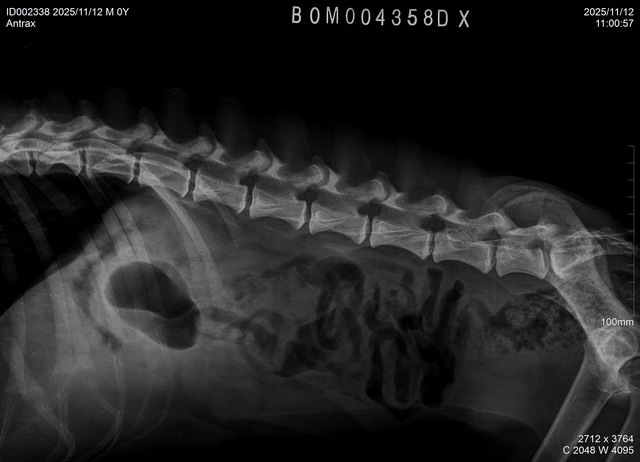

| ANTRAX, DOB July 2 2024, elbows/hips/spine: see x-rays below. ATRAX is almost 2 years old malinois male that was raised in the kennel. He is used to stay both inside the kennel as well as inside of house. He is good with other dogs and has no problem with other animals. ATRAX is a normal social dog and he gets used to the new handler and environment quickly. ANTRAX doesn't have problem with any kind of surface. ANTRAX has excellent ball drive. He is able to search for hidden ball in very hard environments and conditions. He searches with great interest and persistance until he finds the ball. His protection is also excellent. He has fast and hard bites. He is able to work inside and outside of buildings and he can bite on sleeve as well as bite suit. ANTRAX is suitable as a dog for personal protection or as a dual purpose law enforcement dog. |

X-RAYS: